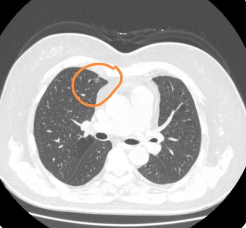

胸腔积液一般是由什么疾病造成的,该如何诊治(图1)

(一)类肺炎性胸腔积液

类肺炎性胸腔积液是指由细菌感染引起的积液。细菌性肺炎是最常见的原因之一。当细菌侵入肺部并引起感染时,机体的免疫反应会导致炎症反应,进而导致胸腔内液体积聚。这种类型的积液通常伴随着其他肺部症状,如咳嗽、呼吸困难和发热。